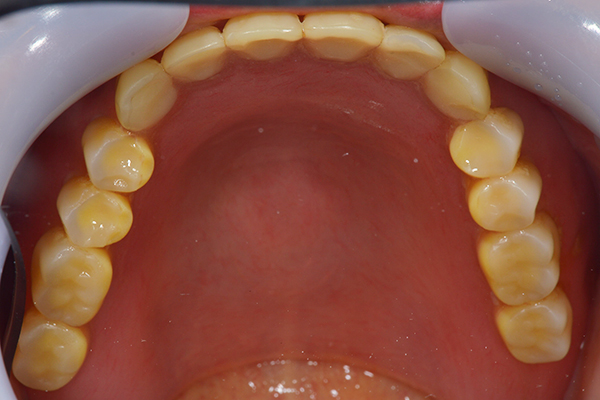

右上と左下の歯がない方です。 上の入れ歯の安定が悪く、作り直したいとのことでいらっしゃいました。 今お使いの上の入れ歯を見てみると、口蓋部分が抜けており、安定性に欠ける構造になっていました。この入れ歯はノンメタルクラスプデンチャーといって、金属のバネを使用しない 入れ歯になります。これは見た目は良いのですが、歯への負担が大きいことと、入れ歯自体がやわらかいため、噛むには不便なことがあります。

入れ歯は極力薄くするために金属を使用しました。しっかり噛める様にするため、ノンメタルクラスプデンチャーにはしませんでした。

上の入れ歯(表)

上の入れ歯(裏)

下の入れ歯

入れ歯を入れた状態のお口の中の写真です。バネも極力目立たないように作成しています。

年齢 70代・女性

主訴 上の入れ歯の安定が悪く、作り直したい

治療期間 5ヶ月

治療費 .診査診断:55,000円

.インプラント埋入:165,000円

.アバットメント:33,000円

.義歯:330,000円

治療方針 右片側のみ奥歯がない方です。

この様な場合入れ歯は反対側に維持を求めるため、大きな入れ歯になりがちです。

そのため違和感が強いことがおおいです。

また、片側だけないですので、安定もむずかしくなります。

そこで、安定をよくするために、右の奥歯の位置にインプラントをいれて、義歯が揺れない様にすることにしました。

治療内容 レントゲンをみて最低限の長さのインプラントを右上の奥歯の位置に埋入しました。インプラントと骨の結合(オッセオインテグレーション)と歯肉の治癒を待ち、アバットメントをいれて型取りをして、入れ歯を作成しました。極力薄くするために、金属をもちいた入れ歯にしました。

特記事項 インプラントは必ず成功するというものではありません。 また治癒も人それぞれで、長くかかることもあります。 入れ歯を入れ終わったあとも、アバットメントが緩んできたり、入れ歯が歯ぐきにあたって痛いところもでてきますので、調整は必要になります。